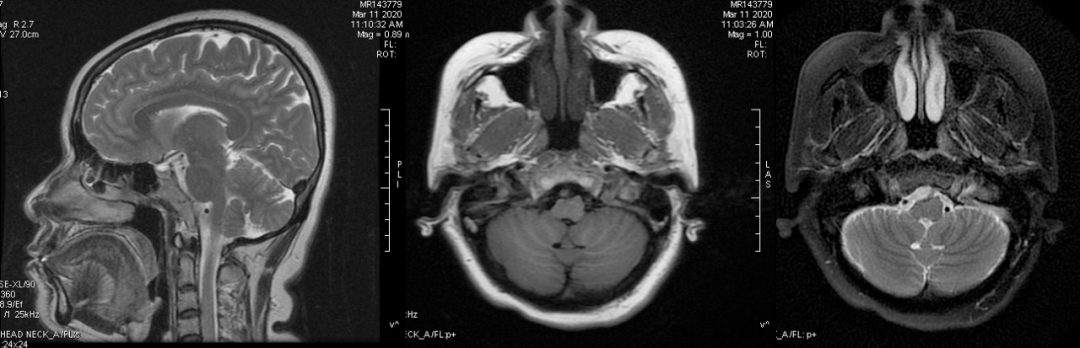

No.1 淋巴瘤

(NK 细胞型淋巴瘤)

(弥漫性大 B 细胞淋巴瘤)

鼻咽部恶性淋巴瘤(nasopharyngeal malignant lymphoma)是指原发于咽淋巴组织(包括腭扁桃体、咽扁桃体、咽鼓管扁桃体和舌扁桃体等组织的 Waldeyer’s 环)的非上皮源性恶性肿瘤,多呈中度恶性。鼻咽淋巴环淋巴瘤占恶性淋巴瘤的 10%-15%,鼻咽部是其好发部位之一,鼻咽部的淋巴瘤绝大多数为 NHL,极少数为霍奇金病(HD)。

鼻咽部 NHL 好发于 40-50 岁男性。起于鼻咽顶后壁扁桃体和咽鼓管扁桃体附近粘膜内淋巴组织,沿鼻咽壁表面弥漫生长,甚至向口咽、鼻腔、鼻窦蔓延,但一般不向粘膜下深层侵犯,与周围组织分界清晰。

由于鼻咽部淋巴组织通过淋巴管网与颈部淋巴结群相连通,肿瘤细胞很容易向颈部淋巴结转移或浸润。

鼻咽部 NHL 病理分三型:B 细胞型(多见)、T 细胞型、NK 细胞型。

MRI 表现:鼻咽后壁及两侧壁不规则软组织肿块,信号多较均匀,T1WI 像呈等信号,T2WI 像呈稍高信号,DWI 像为明显高信号。增强扫描肿块常轻-中度均匀强化,液化坏死少见。颈部淋巴结肿大常见。肿大淋巴结多边缘规则,内部密度或信号均匀,增强扫描轻度强化。对邻近组织侵犯少,肿块与咽后壁头长肌等分界清楚,多无颅底及相邻骨质破坏。鼻咽部肿块虽较明显,但咽旁间隙较清晰,或只有受压改变。